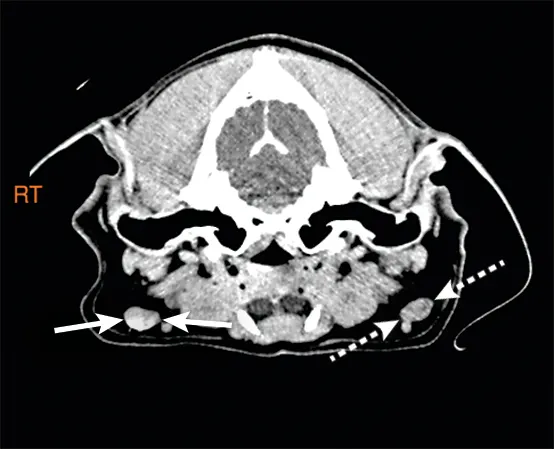

FIGURE 2

CT scan of the same dog in Figure 1. This image is cranial to that shown in Figure 1 and shows the iodinated contrast material in the lymphatics (arrows) as it travels to the SLN.